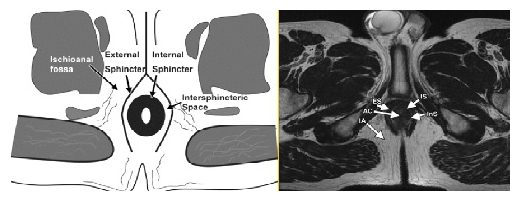

Hiện nay, chụp cộng hưởng từ từ lực cao (High-field MRI) là phương pháp tốt nhất để cung cấp chính xác về đường đi giải phẫu của ống hậu môn, các cơ thắt và tương quan đường rò với cấu trúc sàng chậu.

● Phim chụp cần hiện hình rõ các cấu trúc thành ống hậu môn trực tràng.

● Xác định được đường rò, đường đi và các khối thâm nhiễm xung quanh đường rò và những ổ áp xe nằm sâu không phát hiện được trên lâm sàng.